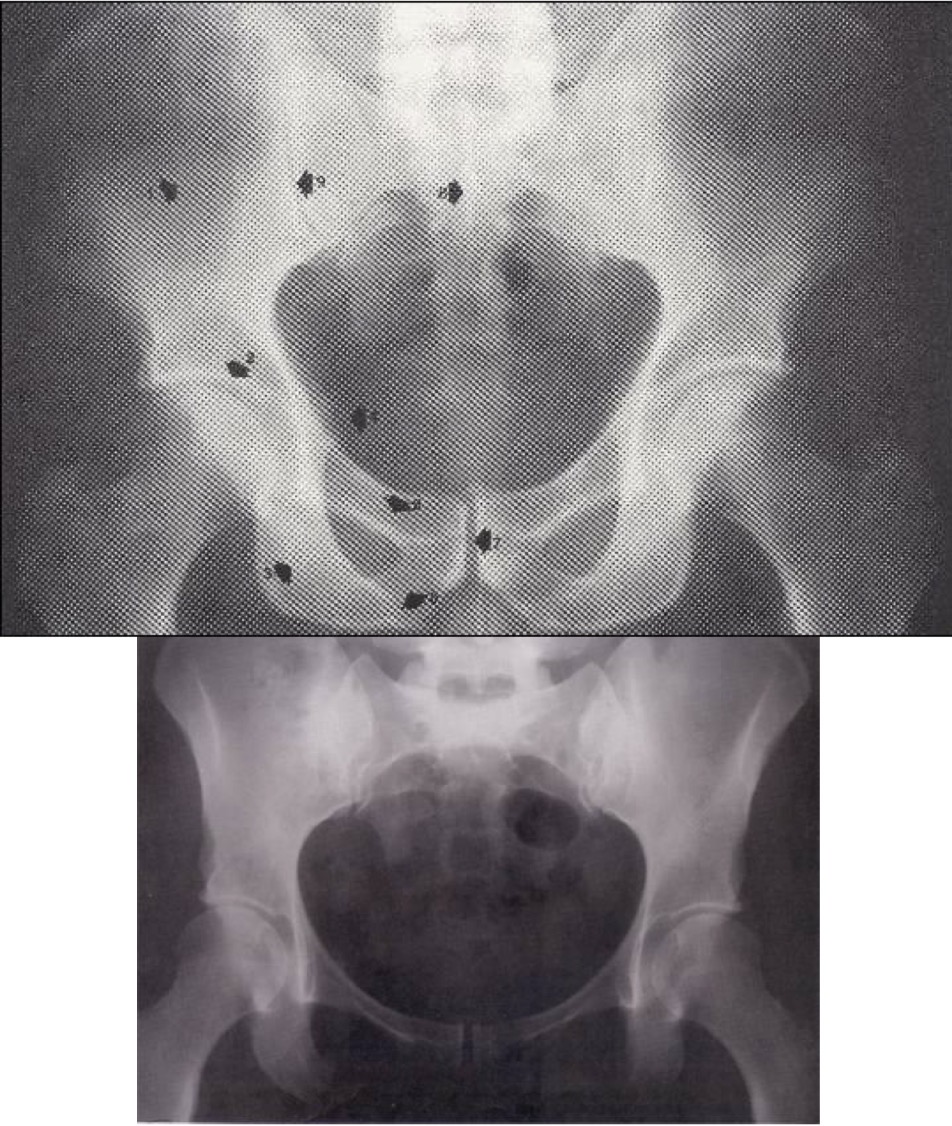

1

Ala ossis ilii

2

Acetabulum

3

Os ischii

4

Spina ischiadica

5

Ramus superior, os pubis

6

Ramus inferior, os pubis

7

Symphysis pubis

8

Sacrum (S2)

9

Art. sacroiliaca